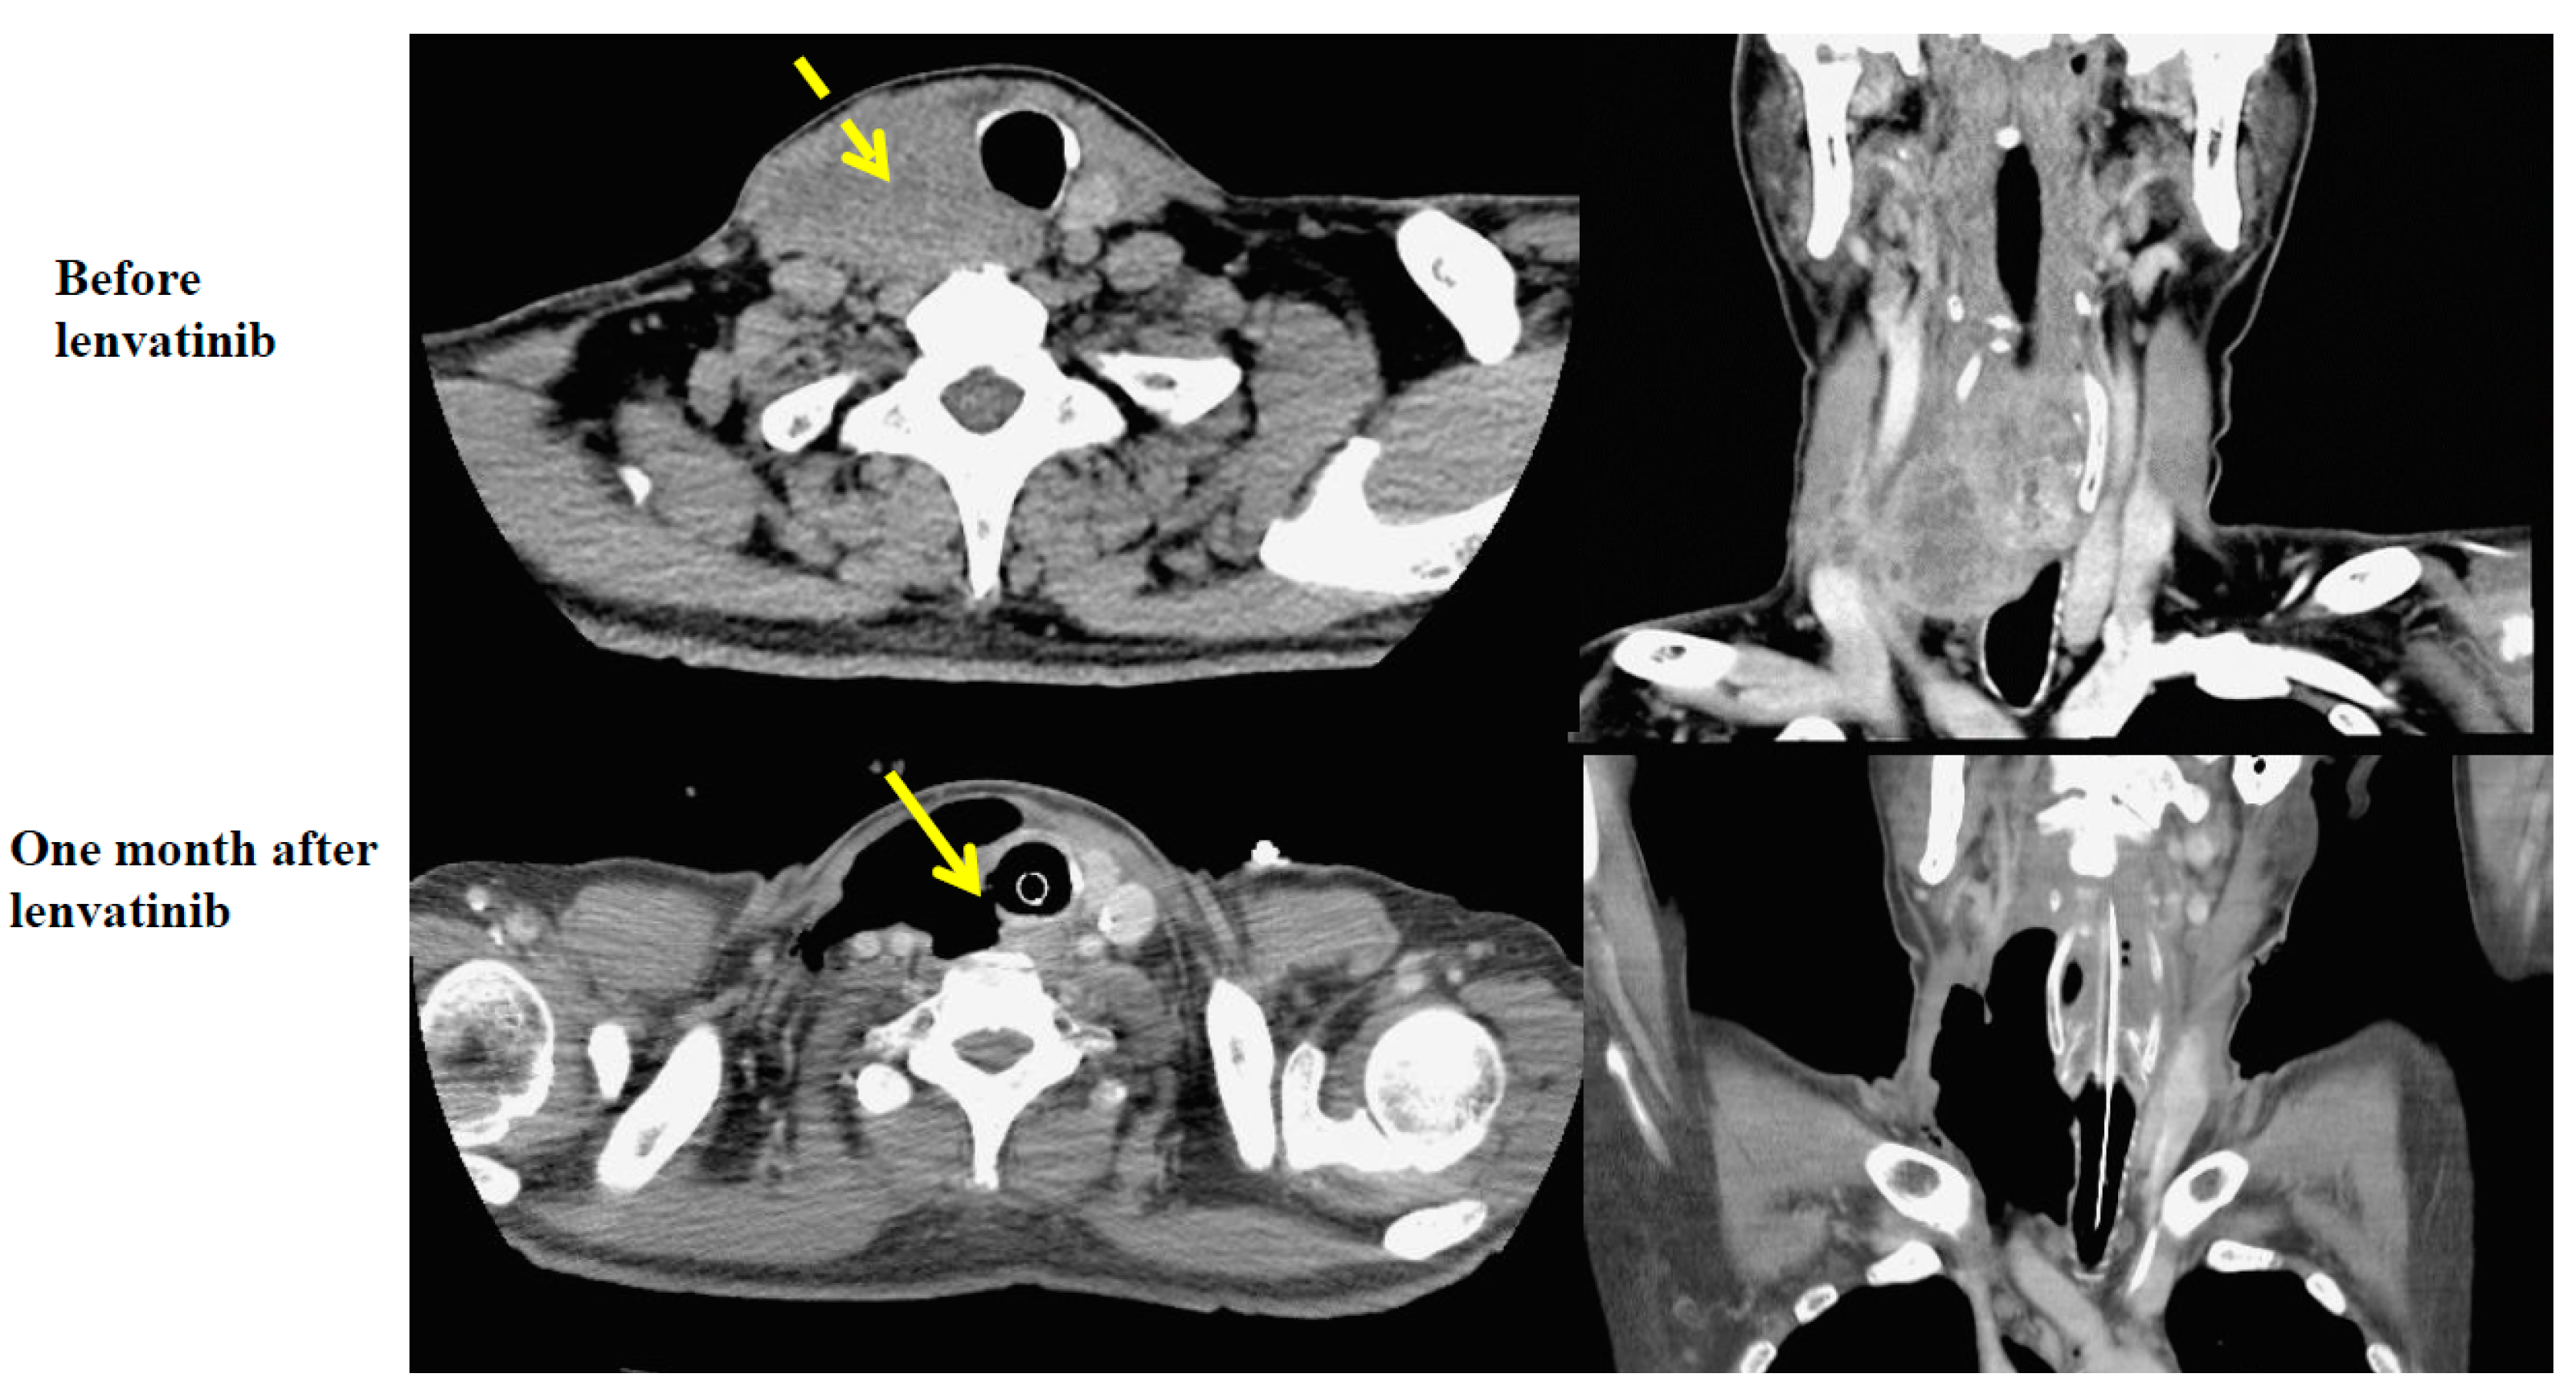

2.1. Case 1